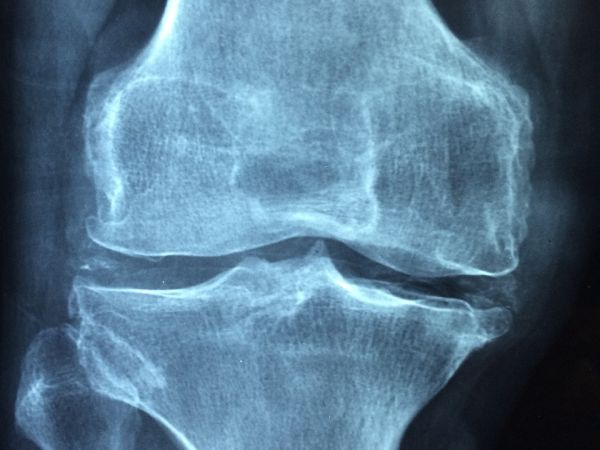

Най-честите симптоми на заболяването са намаляване на ръста, острата болка в гърба, прегърбването.³ Изследването на костната плътност или т.нар. DXA скенер е най-добрият начин за диагностициране на остеопорозата. Остеодензитометрията е безболезнена, продължава около 20 минути, а лъчевото натоварване е изключително ниско. При изследване на лумбалните прешлени то е едва 3 до 5 микросиверта (µSv). За сравнение, ако човек прелита от Европа до Северна Америка ще получи доза радиация, равняваща се на 60 микросиверта. Ранното диагностициране на остеопорозата е особено важно, за да се отложат максимално дълго последствията от загубата на костна маса. Заболяването е добре познато и ранната диагностика означава и по-добро лечение.